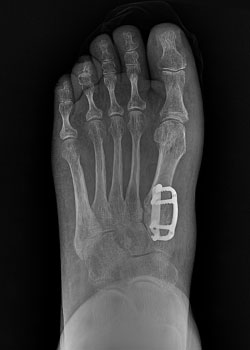

Before